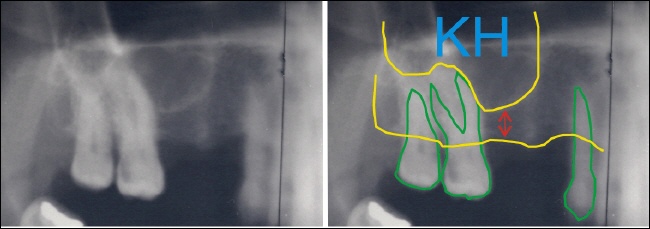

Durch die spezielle Technik des Sinus-Lifts kann der fehlende Knochen mit dem Einsetzen des Implantats aufgebaut werden. Dazu wir die Kieferhöhlenmembran angehoben (daher die Bezeichnung „Lift“) und des entstehende Raum mit Knochen aufgefüllt. Die rote Linie zeigt schematisch die angehobene Membran, die obere gelbe Linie die alte Position der Membran. Die blau schraffierte Fläche ist der gewonnene Kieferknochenabschnitt um das hintere Implantat herum.

Nach fünf Monaten sind die Implantate im Knochen eingeheilt und auch der aufgebaute Knochen ist mit dem umliegenden Knochen fest verwachsen. Die beiden gelben Linien zeigen den festen (der Implantologe spricht von konsolidierten) Knochen zwischen den Implantaten.